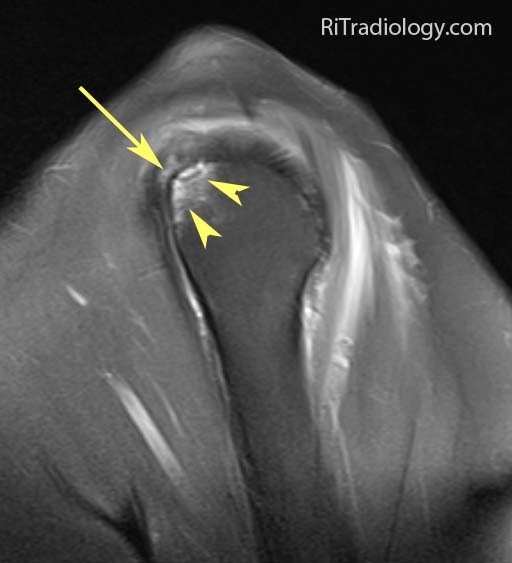

Rim rent tear of the supraspinatus tendon Image

RiT radiology Rimrent Tear of Supraspinatous Tendon Rim Rent Tear Web learn about the causes, symptoms, diagnosis and treatment of rotator cuff tears, a common source of shoulder pain and decreased motion. Web in 1931, ernest codman described the rim rent (partial, articular. Rim Rent Tear.